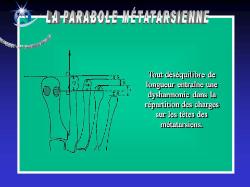

Architecture d’un avant pied normal

La phalange du gros orteil et le premier métatarsien sont pratiquement dans le même alignement.